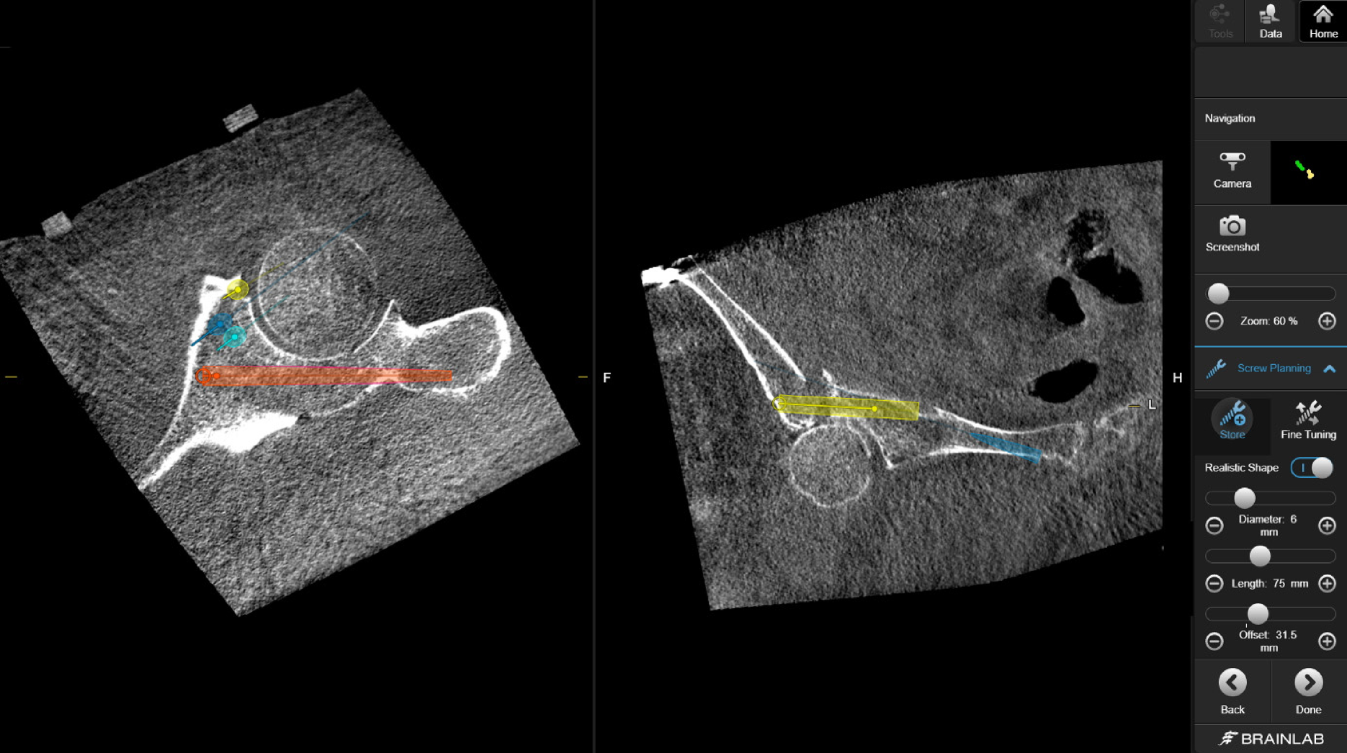

Abb. 8

Über das Interface des Navigationssystems werden mithilfe des Pointerinstrumentariums mögliche Schraubenpositionen eruiert und geplant. Hierbei können bereits die Schraubenlänge und Durchmesser kontrolliert (a) und über das Menü bei Bedarf angepasst (b) und eventuelle Schraubenkorridore so geprüft werden

Abb. 9

Die Planung der Schrauben kann dann nochmals manuell über den Touchscreen feinjustiert werden, um eventuelle intraartikuläre Fehllagen zu vermeiden